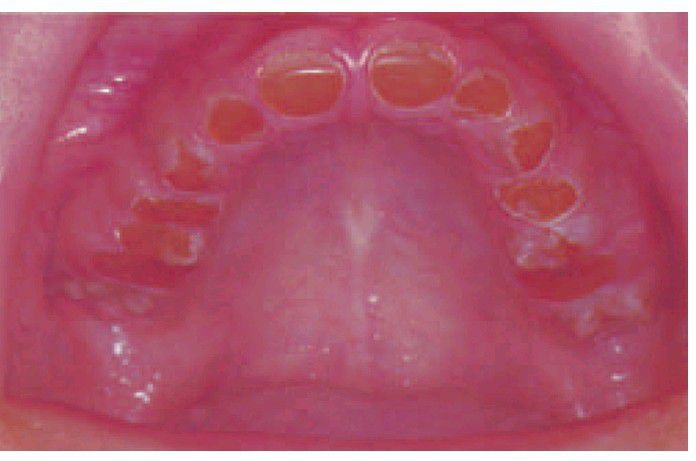

Dentinogenesis imperfecta

. In this 14-year-old, the teeth have worn down to gingival level but the pulp chambers have become obliterated as part of the disease process. Some enamel remains around the necks of the posterior teeth.